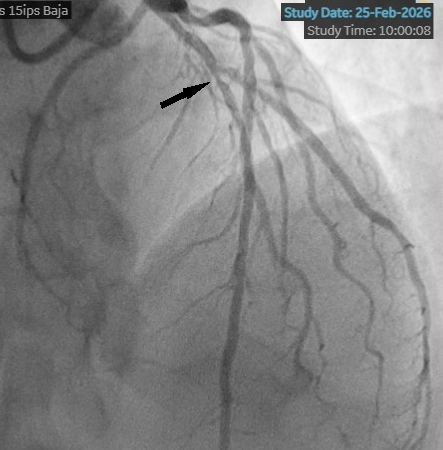

We present the case of a 53-year-old man with a history of Takayasu arteritis, Crohn’s disease, and HLA-B27-negative spondyloarthritis who presented with unstable angina, prompting coronary angiography. Angiography revealed a long, angiographically intermediate lesion in the left anterior descending artery (Figure 1).